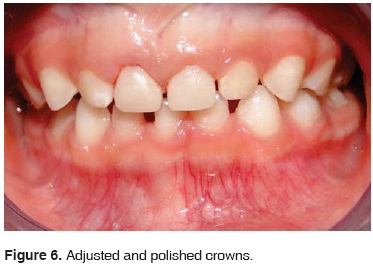

At the second visit, infiltration anesthesia was conducted (2% lidocaine and 1:100,000 epinephrine), in teeth 51 and 61, rubber dam isolation was performed. Preparation of the aforementioned teeth was achieved with a <<pencil shape>> tip burr, wearing down 1 mm at all sides, and rounded borders. Restorations were adjusted, the tooth surface was etched for 15 seconds, and an adhesive layer was applied, polymerization was promoted during 10 seconds, and finally teeth were cemented with dual resin (Figure 4). Restorations had previously been treated with hydrofluoric acid and silane application (Figure 5). Upper anterior restorations were completed preserving function and exhibiting high aesthetic value (Figure 6).